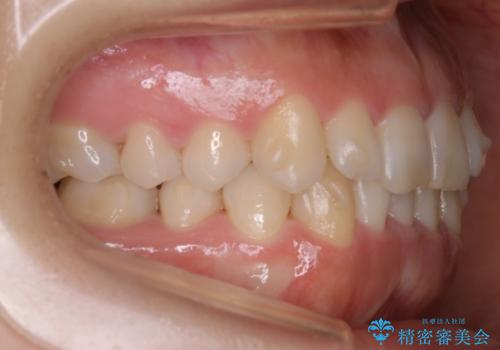

- 前歯のがたつきが気になるとのことで来院されました。

上顎の真ん中の歯の角度が、内側に傾いており、またその隣の歯が、唇側にずれてしまっていました。

下顎については、前歯にがたつきがありました。